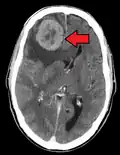

Metastases from the lungs to the brain -